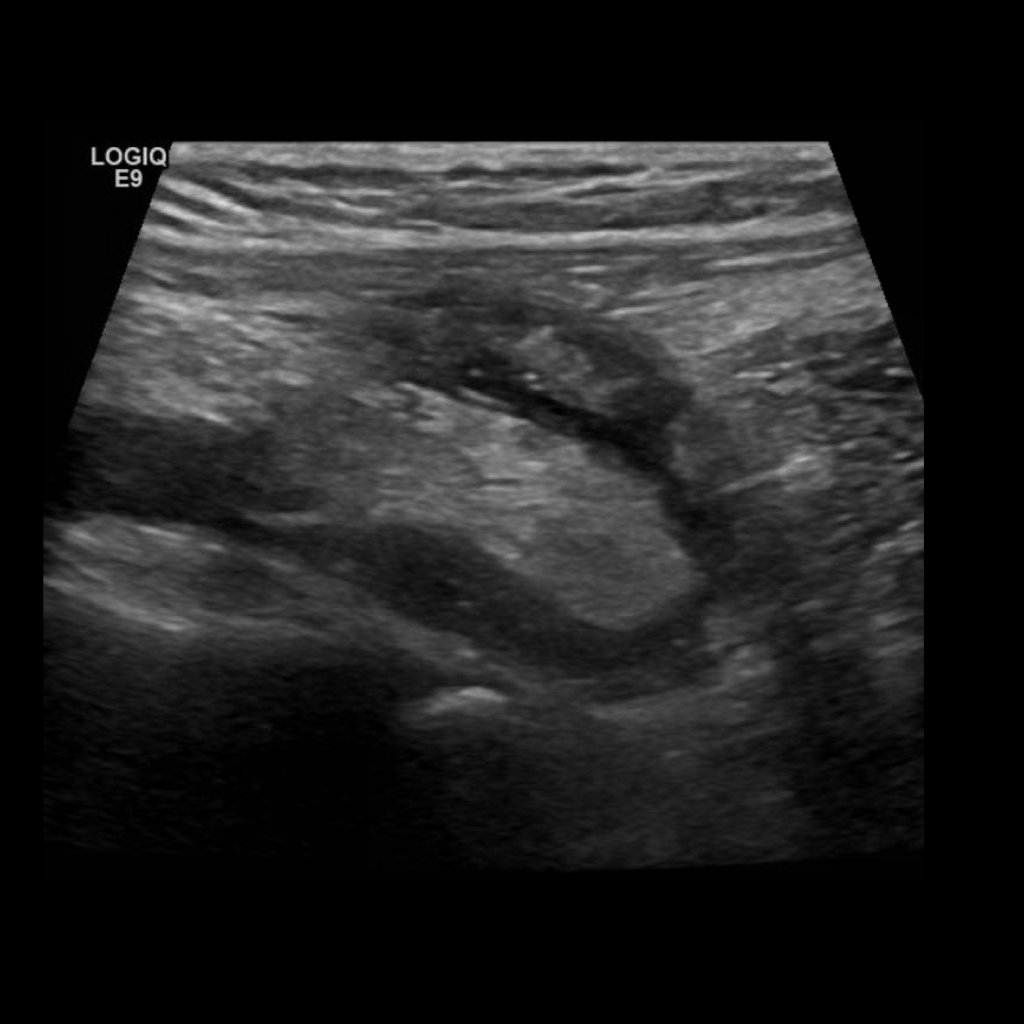

Appendicitis 12

0.9 cm positive appendicitis, with peripheral free fluid, and fat stranding.